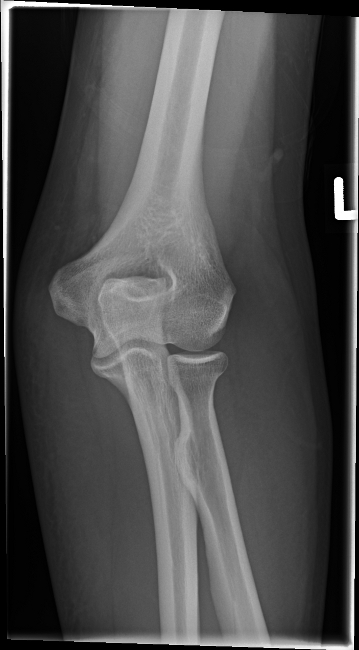

63 jaehrige Frau nach Sturz auf die rechte Huefte. Fraktur?